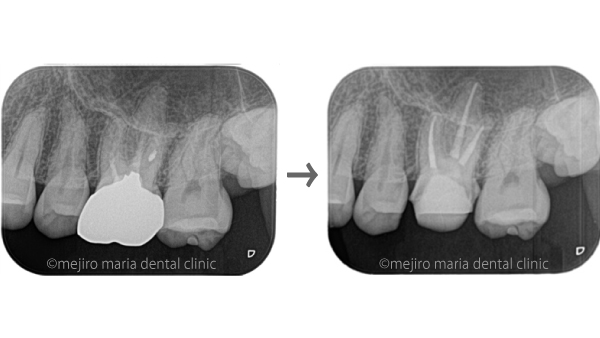

今回の患者様は口腔内の金属を除去し、全ての補綴物を非金属製のもの(ノンメタル)に変えることを希望された患者様です。被せ物の金属を除去する際に、以前に行われた根管治療のやり直しも予防的に行うことをお勧めし、精密根管治療を行うことになりました。

術前より根尖性歯周炎や症状がない症例に関しては90%以上の成功率となるため、ほぼ抜髄処置(初めて根管治療を行う場合)と同じくらいの成功率で治療を終了することができます。

以前に他院で行った保険治療をやり直し、当院で治療されることをご希望された患者様の症例です。金属のインレー、アンレーやアマルガムで最終補綴処置をされている箇所は全てセラミックとレジンにやり直しを行うことになりました。

左上6番(上顎左側第2大臼歯)は既に根管治療が施されており、根尖性歯周炎は根尖に確認されないものの、以前の治療の質は良い状態ではない(質が低い)ことが予想できます。根管治療の質を高める意味合いで再根管治療をご提案させていただきました。